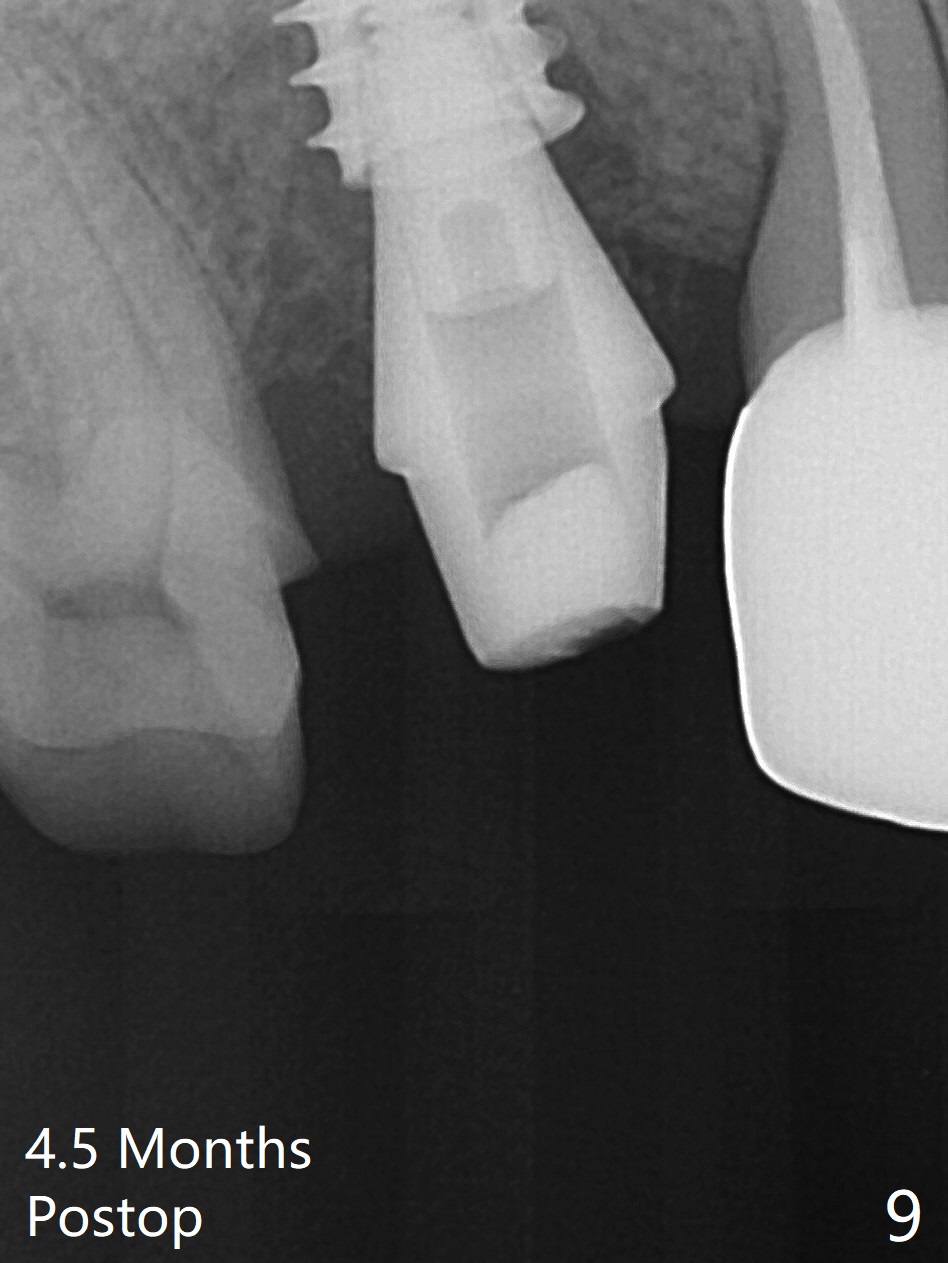

When the tooth #4 with vertical root fracture is extracted, the socket is large, approximately 6x10x10 mm (Fig.1 (mesiodistal x buccopalatal width x depth)). Osteotomy is established in the middle of the socket with 2 mm initial drill for 7 mm, 2.8 and 3.6 mm rounds drills (from DIO Sinus Master Kit) for < 7 mm, and 3.0 and 3.8 mm Magic Expanders. A 4x11 mm dummy implant is placed with insertion torque of 30 Ncm (Fig.2,3 (^: sinus floor)). There is a gap between the socket wall and the implant (*). To reduce the gap and periimplantitis, a 5x11 mm IBS implant is placed with insertion torque > 50 Ncm after further osteotomy using Magic Drills (Fig.4,5). Following placement of 5.5x4(4) mm abutment (A) and bone graft (data not shown), a splinted provisional is fabricated at #3 and 4. The provisional is stable 3 months postop (Fig.6,7). The peri-implant gaps (Fig.4,5) seem to disappear (Fig.6) with the help of bone graft. Bone graft appears to remain between the implant fins (Fig.7 arrows). Impression is taken 4.5 months postop (Fig.8,9). The abutment dislodges 4 months post cementation. After retightening, there is clearance for shim after use of 2 layers of thick articulating paper. Is the abutment screw too short? Or Titanium V is too hard for welding? The abutment/crown dislodges again 1 year 3 month post cementation; it appears that the fact that the implant is placed deep contributes to abutment screw loosening (Fig.10,11). An abutment screw will be buried inside the implant well 10 days post initial retightening.